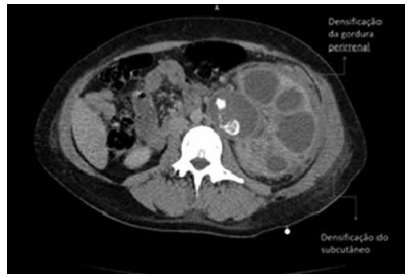

Mulher de 58 anos apresenta-se com dor no flanco, febre e mal-estar prolongado. Ela tem um histórico de infecções recorrentes do trato urinário e cálculos renais. Exames de urina revelam piúria e bacteriúria. Uma tomografia computadorizada mostra uma massa renal com características de “pata de urso” e densificação da gordura perirrenal e densificação do subcutâneo.

(https:// drpixel.fcm.unicamp.br)

Com base na história clínica e no exame de imagem, assinale a alternativa que apresenta o diagnóstico correto.